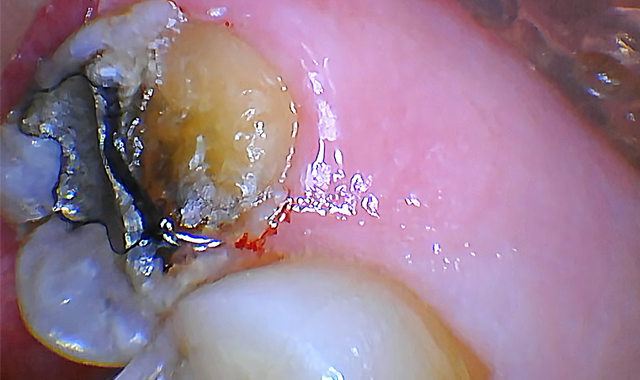

A pre-operative diagnostic radiograph showed no endodontic pathology. She is in excellent periodontal health (Fig. 1). Oral evaluation of the patient indicated that the palatal cusp of #15 fractured subgingivally to the level of the alveolar crest (Fig. 2).

Fig. 1 Fig. 2